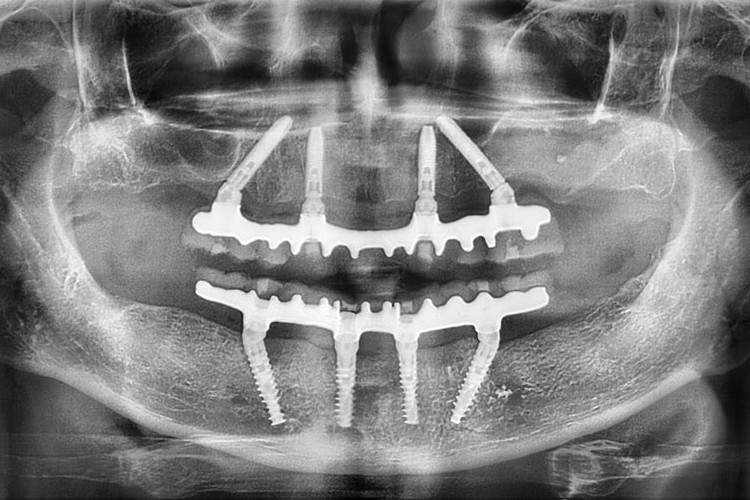

All-on-4 на рентгеновских снимках

![]() |